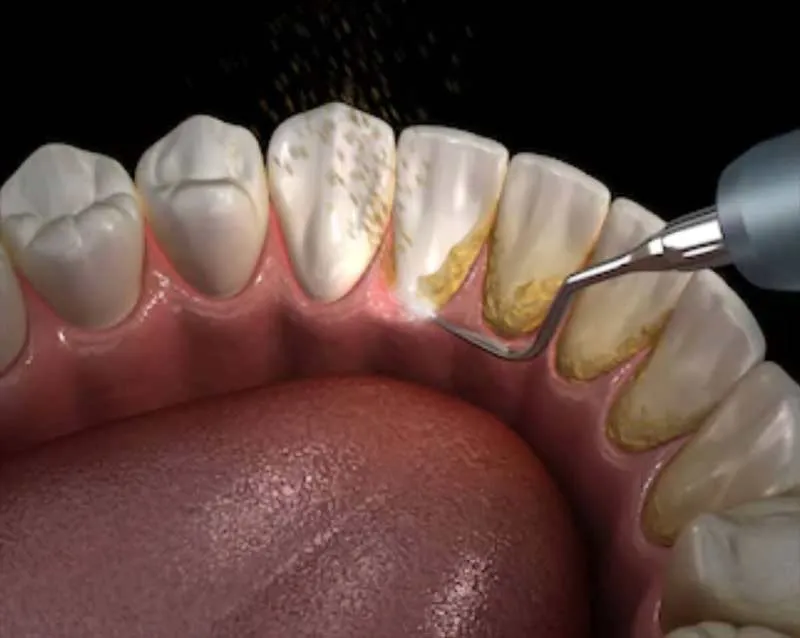

Skaling: Czym jest i dlaczego to pierwszy krok do czystych zębów?

Skaling to podstawowy zabieg higienizacyjny, który polega na usunięciu twardego kamienia nazębnego. Kamień powstaje, gdy płytka bakteryjna nie jest regularnie usuwana i ulega mineralizacji. Początkowo jest żółtawy, ale z czasem pod wpływem barwników ciemnieje, stając się brązowy. Stomatolog używa do tego celu specjalnych narzędzi ultradźwiękowych (skaler) lub ręcznych. Skaling jest kluczowy nie tylko dla estetyki, ale przede wszystkim dla zdrowia dziąseł i całej jamy ustnej, ponieważ kamień nazębny jest siedliskiem bakterii.

Piaskowanie zębów: Jak działa "myjka ciśnieniowa" dla Twojego uśmiechu?

Po skalingu często wykonuje się piaskowanie. Wyobraź sobie "myjkę ciśnieniową" dla Twoich zębów to właśnie tak działa piaskowanie! Zabieg polega na usunięciu osadów i drobnych przebarwień za pomocą strumienia wody, powietrza i drobnego proszku (piasku dentystycznego). Dzięki temu docieramy do trudno dostępnych miejsc, takich jak bruzdy czy przestrzenie międzyzębowe, a także skutecznie usuwamy przebarwienia po kawie, herbacie czy papierosach. Dodatkowo piaskowanie wygładza powierzchnię zębów, co utrudnia ponowne osadzanie się nalotu.